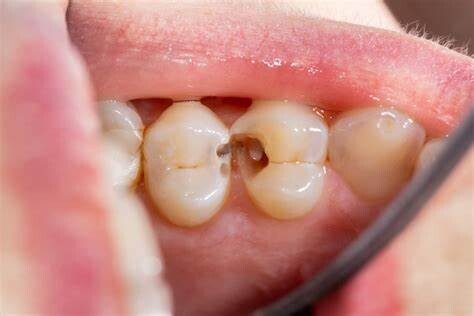

Yes, even when you take care of your enamel, you can still end up with a cavity between your teeth. This has a technical term called an interproximal cavity. It forms like other cavities: when the enamel is worn away and bacteria are able to get into the tooth.

A cavity is an easily preventable dental condition in which the hard surface of your teeth (the enamel) ends up with a tiny hole in it. This permanent damage is caused when the bacteria stick to the tooth.

As you engage in frequent snacking, eat sugary foods or drink sugary drinks, and don't effectively clean right after, the food particles form dental plaque.

As plaque, bacteria sticks to the enamel and decays the tooth. If you don't remove decay fast, it turns into a hole that requires a large filling to fix it. However, if it's caught early, the enamel could be recalcified with fluoride gel.

Browning or yellowing teeth - When you see dark spots on your teeth, it's not normal. This is a sign that a hole is beginning to form inside the tooth. It can be recalcified with fluoride gel if you catch it before tooth decay becomes a hole. At that point, the dentist can use tooth colored filling material to cover the hole, but it can't be reversed.